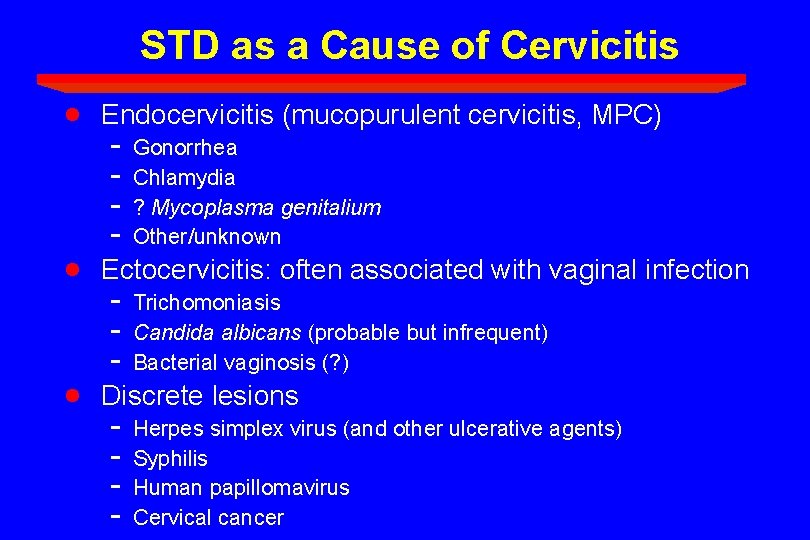

STD as a Cause of Cervicitis · · · Endocervicitis (mucopurulent cervicitis, MPC) - Gonorrhea Chlamydia ? Mycoplasma genitalium Other/unknown Ectocervicitis: often associated with vaginal infection - Trichomoniasis Candida albicans (probable but infrequent) Bacterial vaginosis (? ) Discrete lesions - Herpes simplex virus (and other ulcerative agents) Syphilis Human papillomavirus Cervical cancer